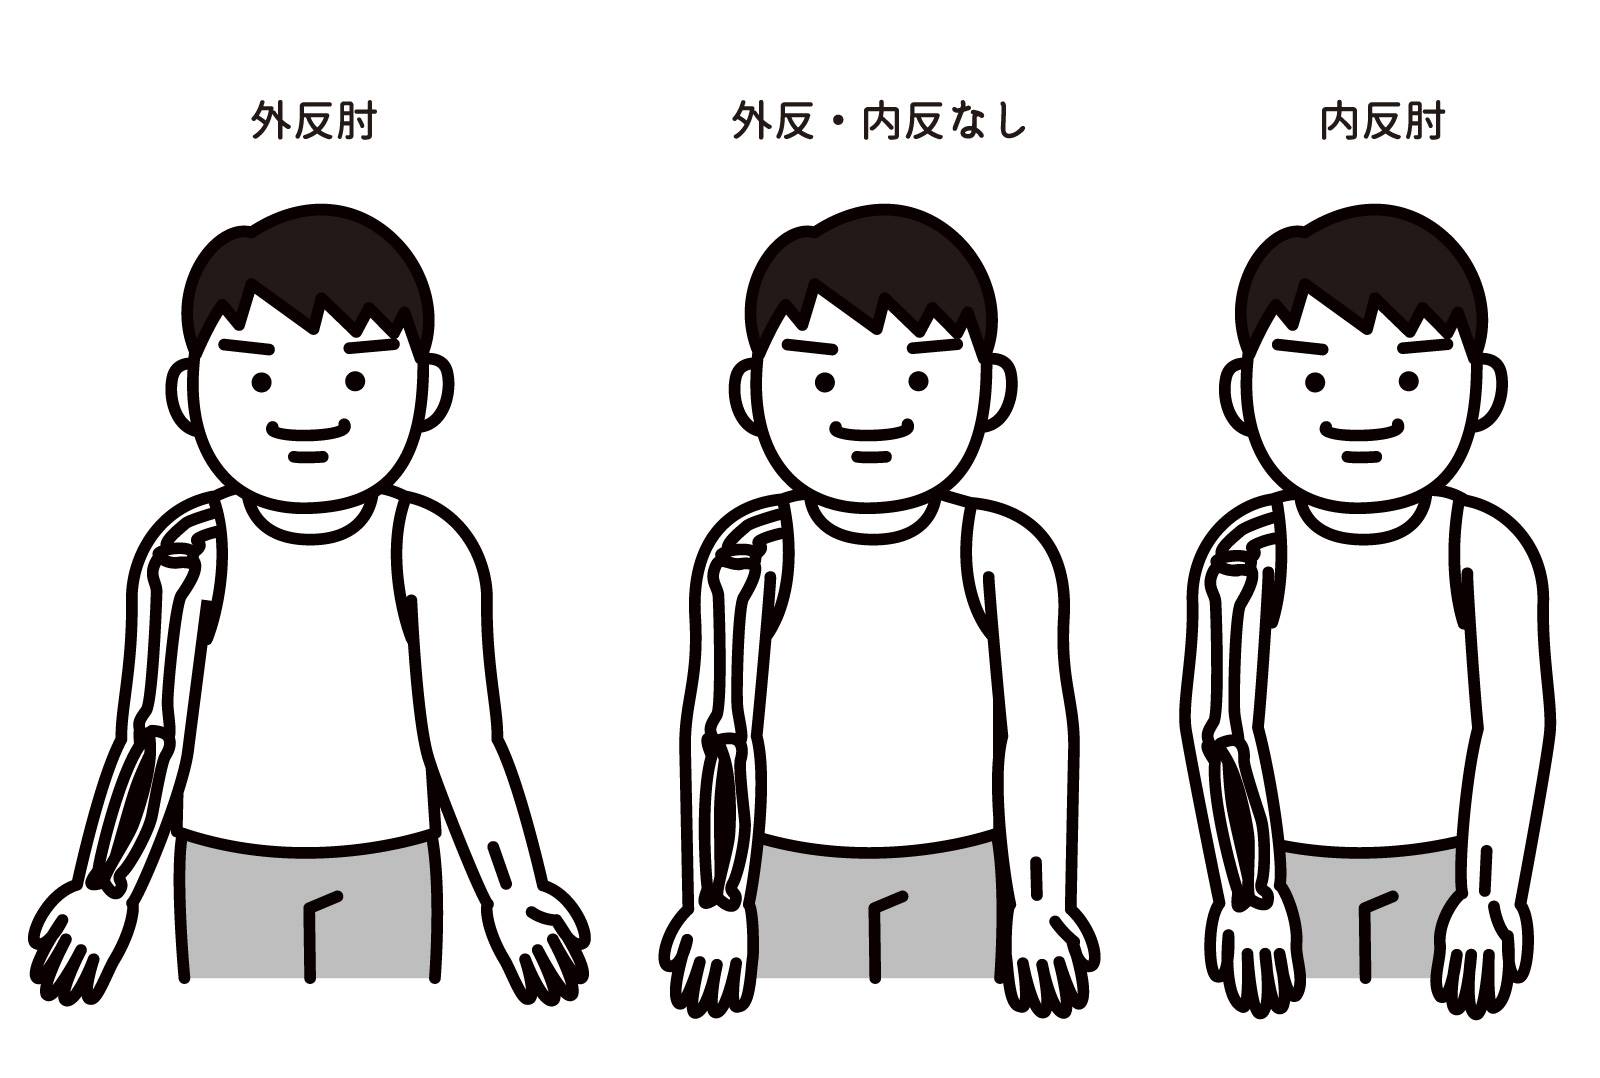

1-3-2.内反肘(ないはんちゅう)・外反肘(がいはんちゅう)|骨の変形による痛み

「子どもの頃に肘を骨折したことがある」という方、肘の形に違和感を覚えたことはありませんか?

そのような方は、成長とともに肘が変形し「内反肘(ないはんちゅう)」や「外反肘(がいはんちゅう)」という状態になっている可能性があります。

内反肘とは、腕をまっすぐに伸ばしたときに、肘が内側(小指側)に曲がっている状態を指します。一方、外反肘とは、腕をまっすぐに伸ばしたときに、肘が外側(親指側)に曲がっている状態を指します。

内反肘や外反肘になると、肘関節のバランスが崩れ、特定の部分に過度な負担がかかるようになります。その結果、筋肉や腱、靭帯にストレスがかかり、炎症や痛みを引き起こすことがあるのです。

特に、スポーツや仕事などで肘を頻繁に使う人は、痛みが出やすくなります。

多くの場合、子どもの頃の骨折が原因で、骨折の治療が完全にできなかった場合に起こる症状です。

内反肘や外反肘は、比較的まれなケースですが、子どもの頃に肘を骨折した経験があり、肘の形や痛みに違和感がある場合は、一度整形外科を受診し、専門医に相談することをおすすめします。